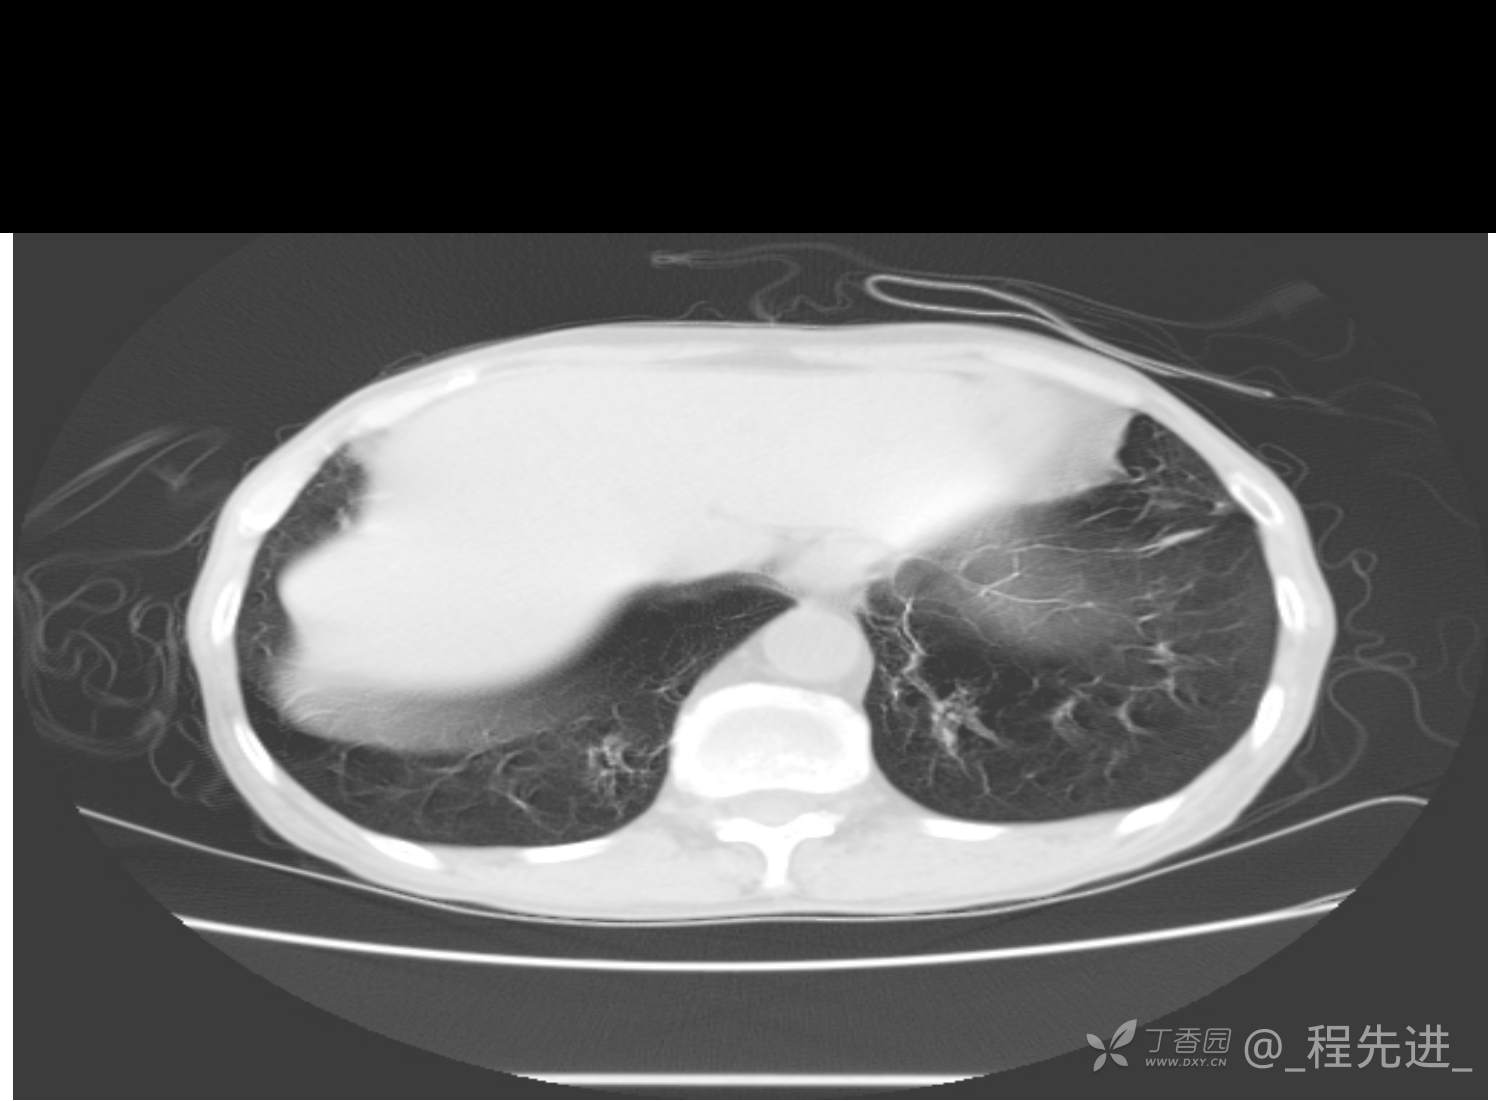

患者性别:男

患者年龄:81岁

简要病史:反复咳嗽、咳痰20余年,加重1周。两肺呼吸音低,可闻及散在干湿啰音。